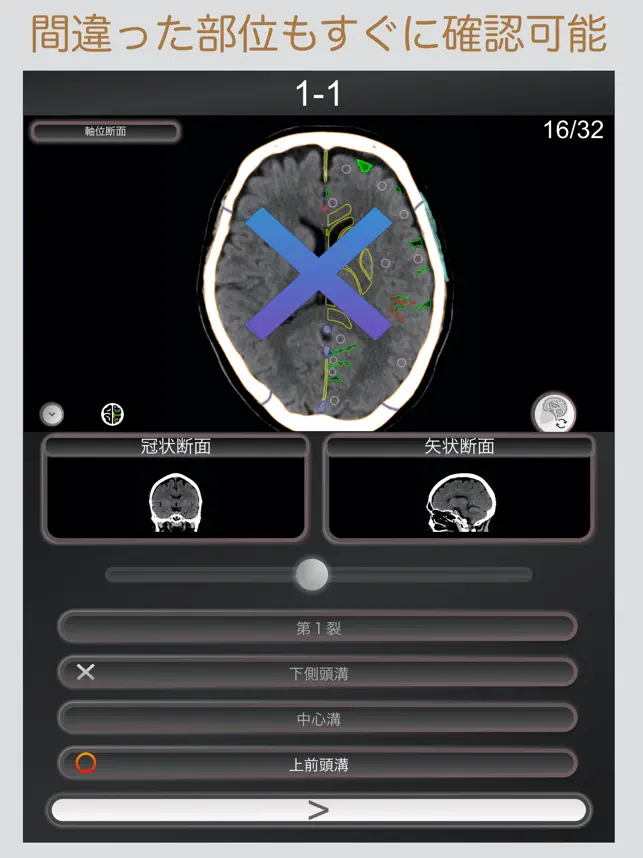

CT PassQuizは人体解剖を学びたい全ての人の為に作られた解剖学習アプリです。

現在、私達は日常的に3D画像を目にする様になりましたが、本当に立体的に理解する為には、平面の画像を分析して頭の中で再構築する作業が必要です。

このアプリはCT画像に表示された解剖名称をクイズ形式で出題し、軸位断面・冠状断面・矢状断面を切り替えて4択問題から解答を選ぶことで効率的に画像解剖を学ぶ事ができます。

【収録画像】

頭部CT画像

軸位断面 スライス枚数:32枚

冠状断面 スライス枚数:41枚

矢状断面 スライス枚数:31枚

解剖名数:167項目

【問題数】

Section:20(各10問) 計:200問

【補助機能】

■断面の切り替え表示

サブ画面を選択する事で、軸位断面・冠状断面・矢状断面の切り替えて、様々な断面を確認する事が可能です。

■選択可能範囲の表示

画像上の解剖範囲を表示する事で周りの解剖名称を確認しながらの解答が可能です。

■画像条件の切り替え

脳実質条件・骨条件の切り替え表示が出来ます。

■拡大表示

拡大・縮小ボタンもしくは、画面をピンチインアウトすることで画像の大きさを変更出来ます。